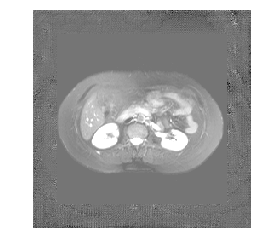

Medical image segmentation methods normally perform poorly when there is a domain shift between training and testing data. Unsupervised Domain Adaptation (UDA) addresses the domain shift problem by training the model using both labeled data from the source domain and unlabeled data from the target domain. Source-Free UDA (SFUDA) was recently proposed for UDA without requiring the source data during the adaptation, due to data privacy or data transmission issues, which normally adapts the pre-trained deep model in the testing stage. However, in real clinical scenarios of medical image segmentation, the trained model is normally frozen in the testing stage. In this paper, we propose Fourier Visual Prompting (FVP) for SFUDA of medical image segmentation. Inspired by prompting learning in natural language processing, FVP steers the frozen pre-trained model to perform well in the target domain by adding a visual prompt to the input target data. In FVP, the visual prompt is parameterized using only a small amount of low-frequency learnable parameters in the input frequency space, and is learned by minimizing the segmentation loss between the predicted segmentation of the prompted target image and reliable pseudo segmentation label of the target image under the frozen model. To our knowledge, FVP is the first work to apply visual prompts to SFUDA for medical image segmentation. The proposed FVP is validated using three public datasets, and experiments demonstrate that FVP yields better segmentation results, compared with various existing methods.